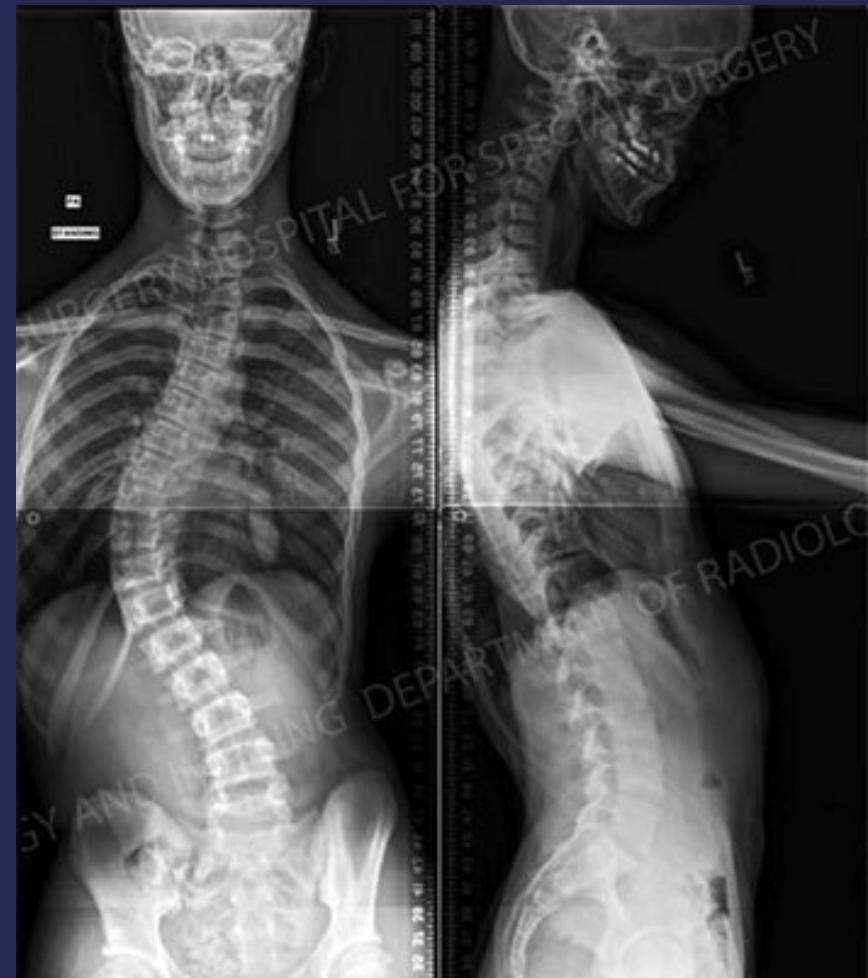

Clinical Features

- Shoulders at different heights – one shoulder blade more prominent

- Head not centered directly above the pelvis

- Raised, prominent hip

- Rib cages at different heights

- Uneven waist

- Skin texture changes overlying the spine

- Leaning of entire body to one side

Imaging

- X-ray:

- AP and LAT of entire spine (Cobb angle measurement)